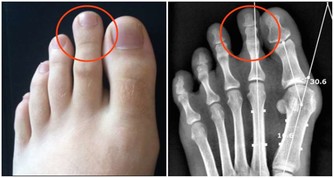

4、影響長高

吃糖過多,還可以影響鈣質代謝。

有些學者認為吃糖量如果達到總食量的16-18%,就可使體內鈣質代謝紊亂,妨礙體內的鈣化作用。

據日本一項調查表明,小兒骨折率有所增加,他們認為糖過多是造成骨折的重要原因。